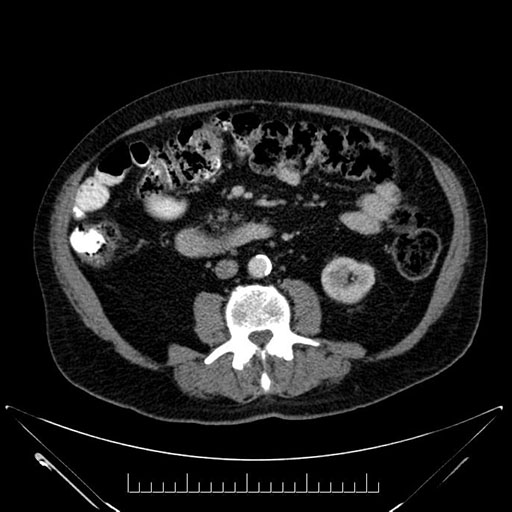

Coronal - stented